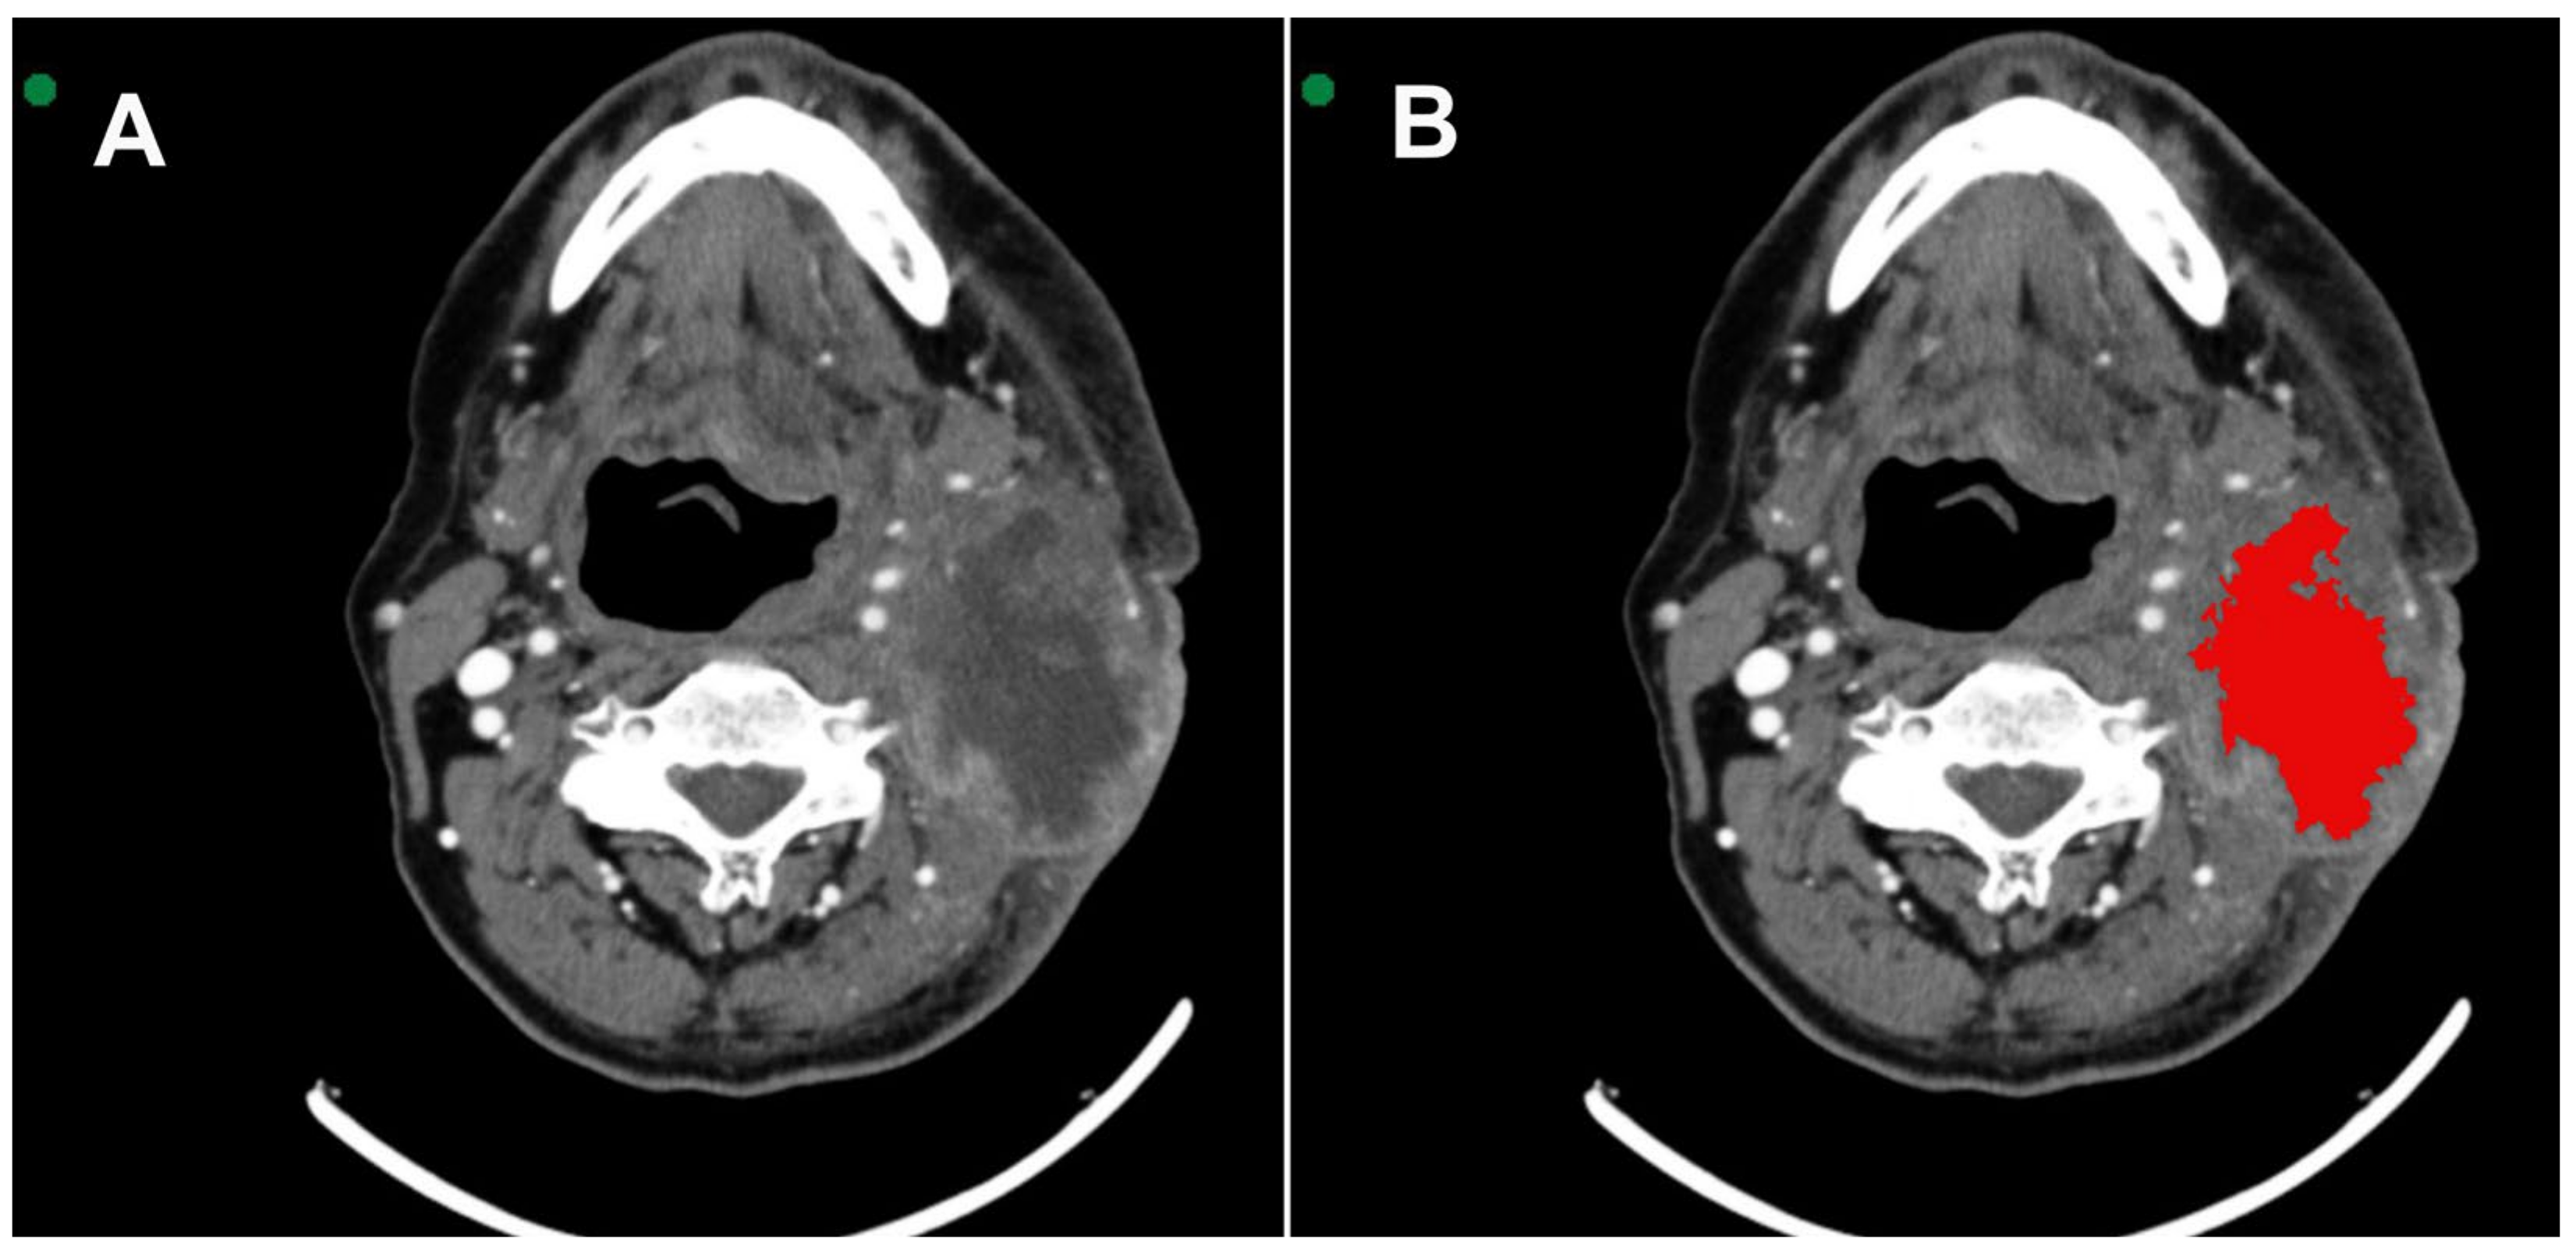

2.3. Image Processing and Analysis